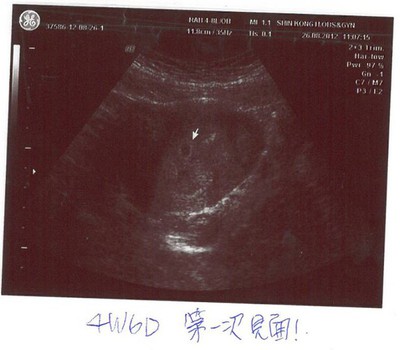

For my baby- 8/25 發現4W6D

4W6D.jpg孩子,謝謝你,願意來到這裡,選擇我和我先生做為你的爸爸和媽媽。媽媽患有嚴重的多囊性卵巢症候群,除了發胖外,連帶人工受孕也進行的相當不順利,之前藥物的副作用,常讓我整個六日都躺在床上不能...